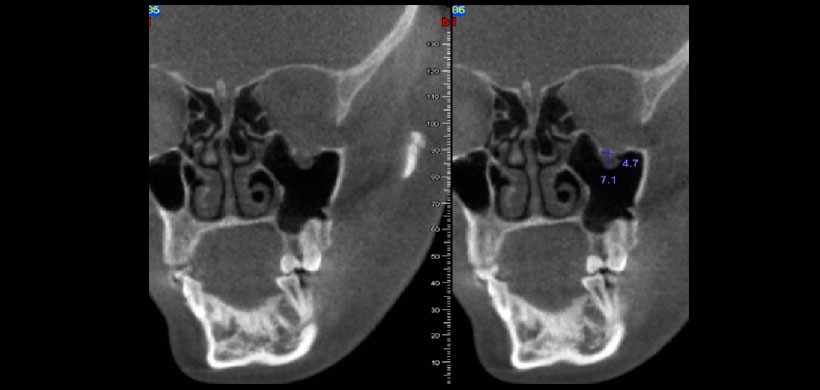

Figura 5: Aplicación de la TCHC en el diagnóstico de obstrucciones de las vías aéreas. En el presente caso se muestra el aumento de tamaño de la amígdala adenoidea ocasionando una obstrucción de la vía aérea (nasofaringe)